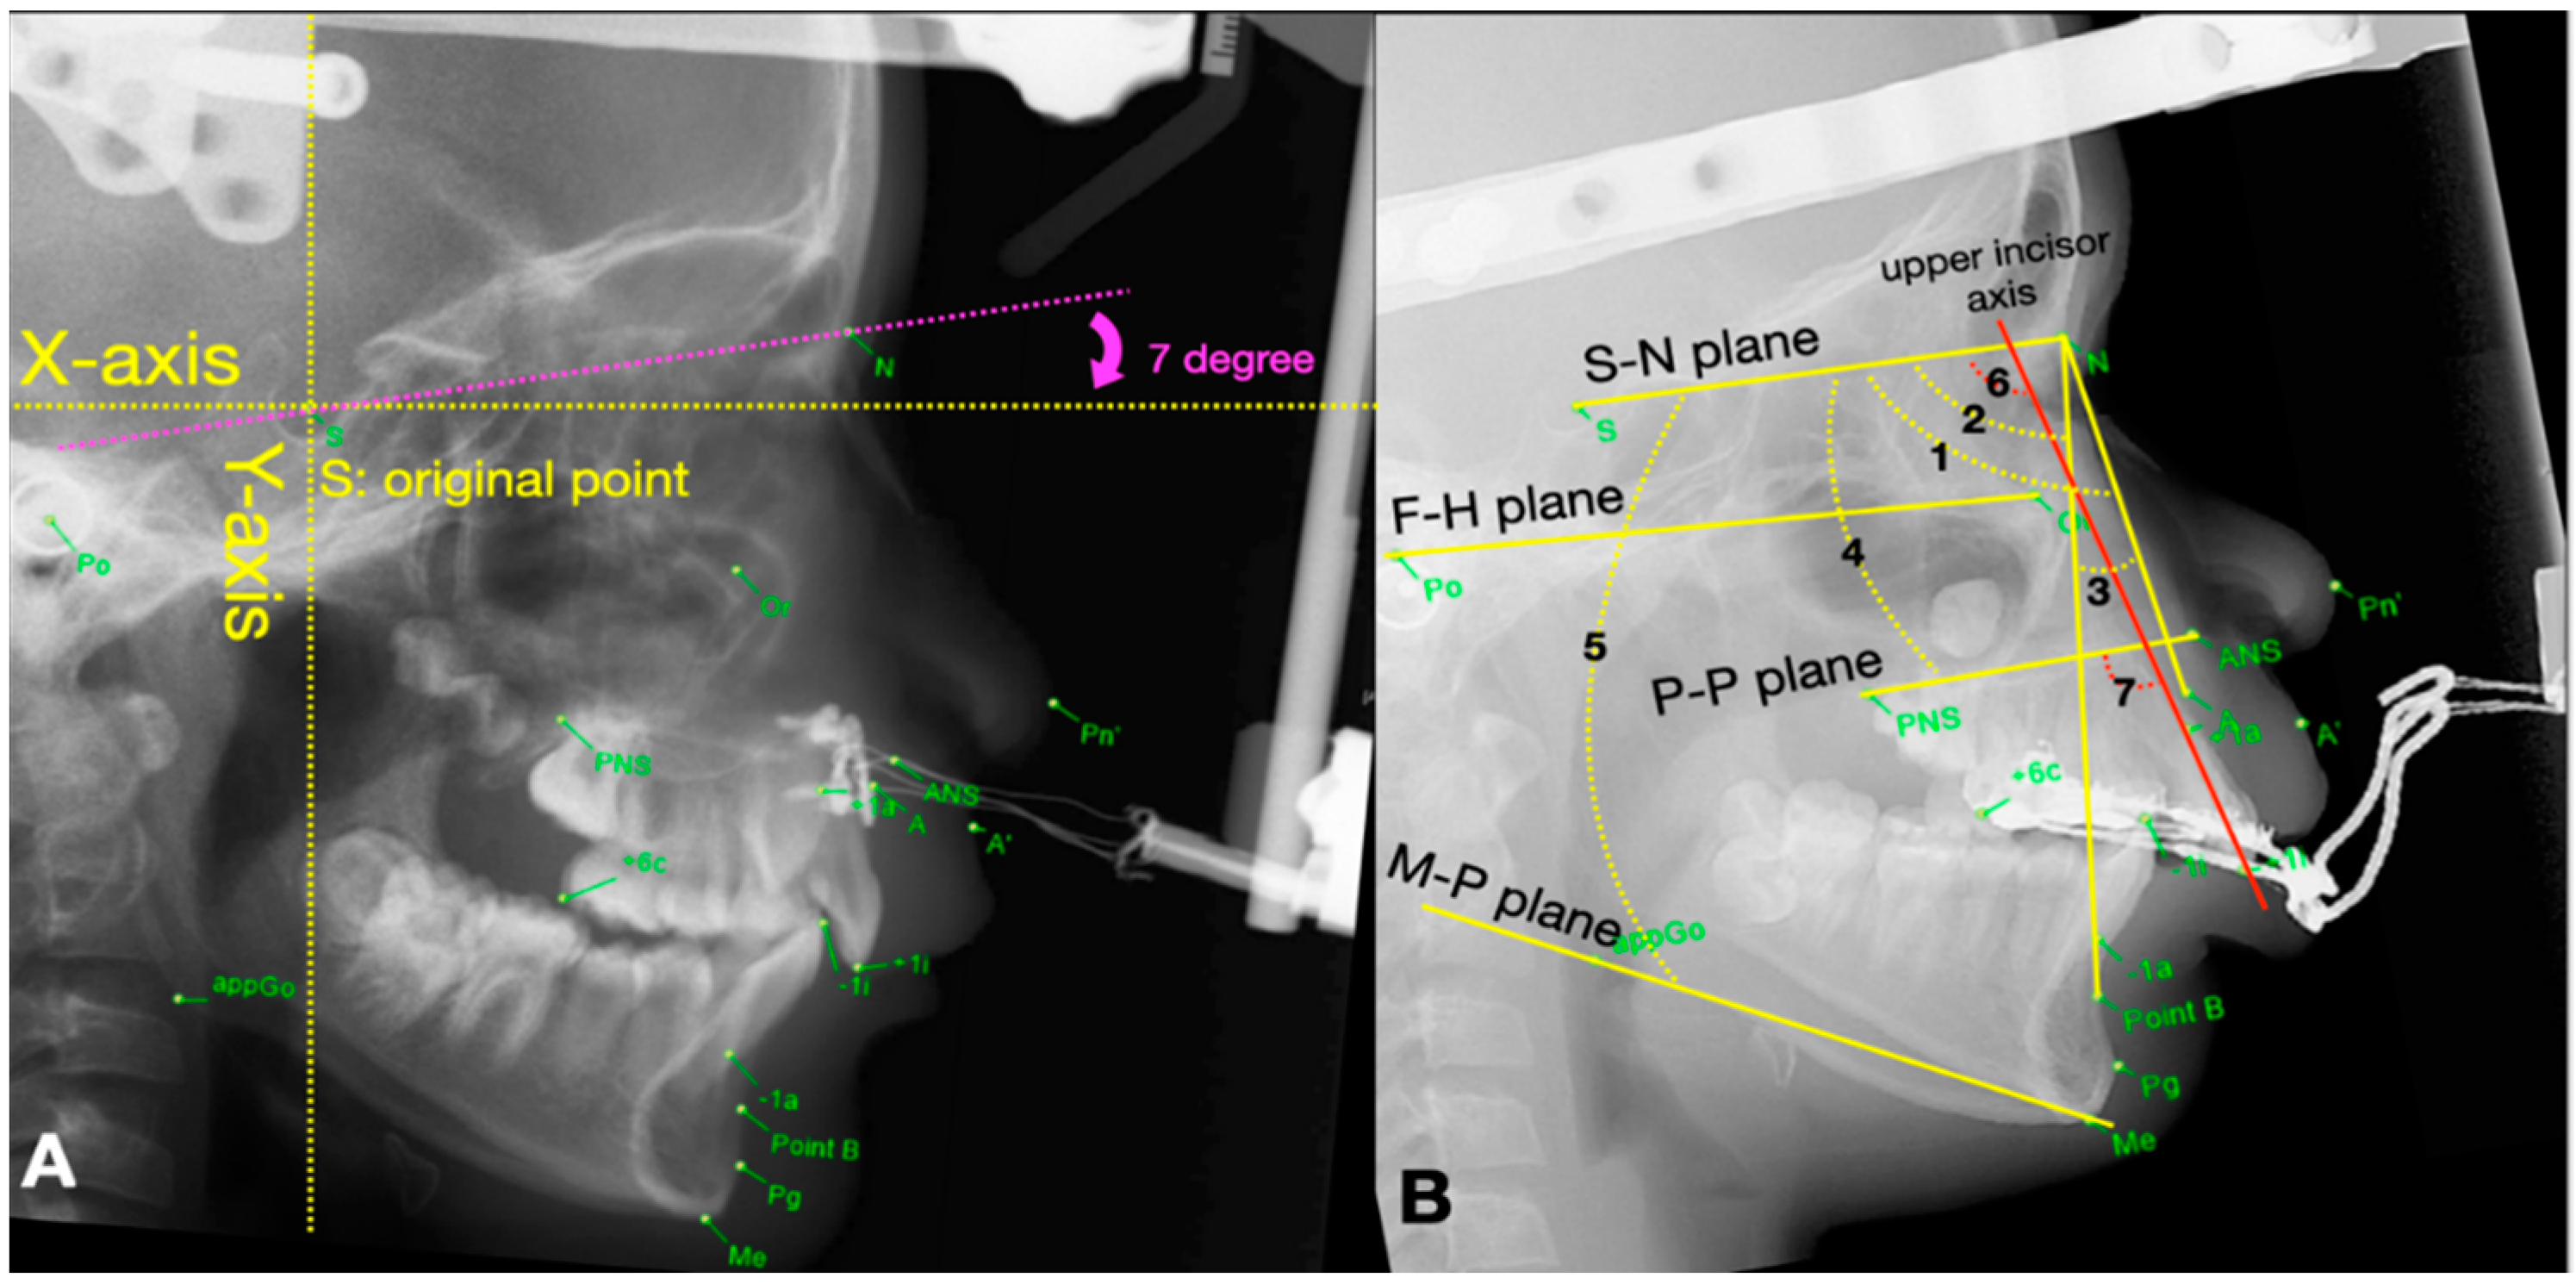

The AudaxCeph Empower software (VER5.2, Ljubljana, Slovenia) was used to analyze the changes of parameters among the above 4 stages (T0-T3). An x-y coordinate system was designed to measure the displacement of selected landmarks in two dimensions on the serial cephalograms. A horizontal reference line approaching the true horizontal line was constructed 7 degrees below the sella–nasion (S-N) line as the X-axis [13]. Then the Y-axis was determined by drawing a vertical reference line perpendicular to the X-axis by intersecting the line at the Sella point. Therefore, the assessment of linear and angular parameters derived from each landmark on cephalograms could be measured according to the X-Y coordinate system, and the measurements were recorded between each phase by a single examiner (C.Y Tsai) (Figure 3A,B). Table 1 illustrated the definition of linear parameters in relation to the X-, Y-axis.

Figure 3. The lateral cephalograms of (A) Bone-borne RED with transcutaneous wire system present with cephalometric landmarks in relation to the X-Y coordinate system (B) traditional Tooth-borne RED with intra-oral splint, present with reference lines: S-N plane (S-N, sella-nasion plane); F-H plane (Po-Or, Frankfort plane); P-P plane (PNS-ANS, palatal plane); M-P plane (Go-Me, mandibular plane); upper incisor axis (+1i-+1a), and skeletal angular variables: 1, SNA; 2, SNB; 3, ANB; 4, SN-PP; 5, SN-MP, and dental angular variables: 6, U1-SN (upper incisor axis to S-N); 7, U1-PP (upper incisor axis to palatal plane) that selected in this study.